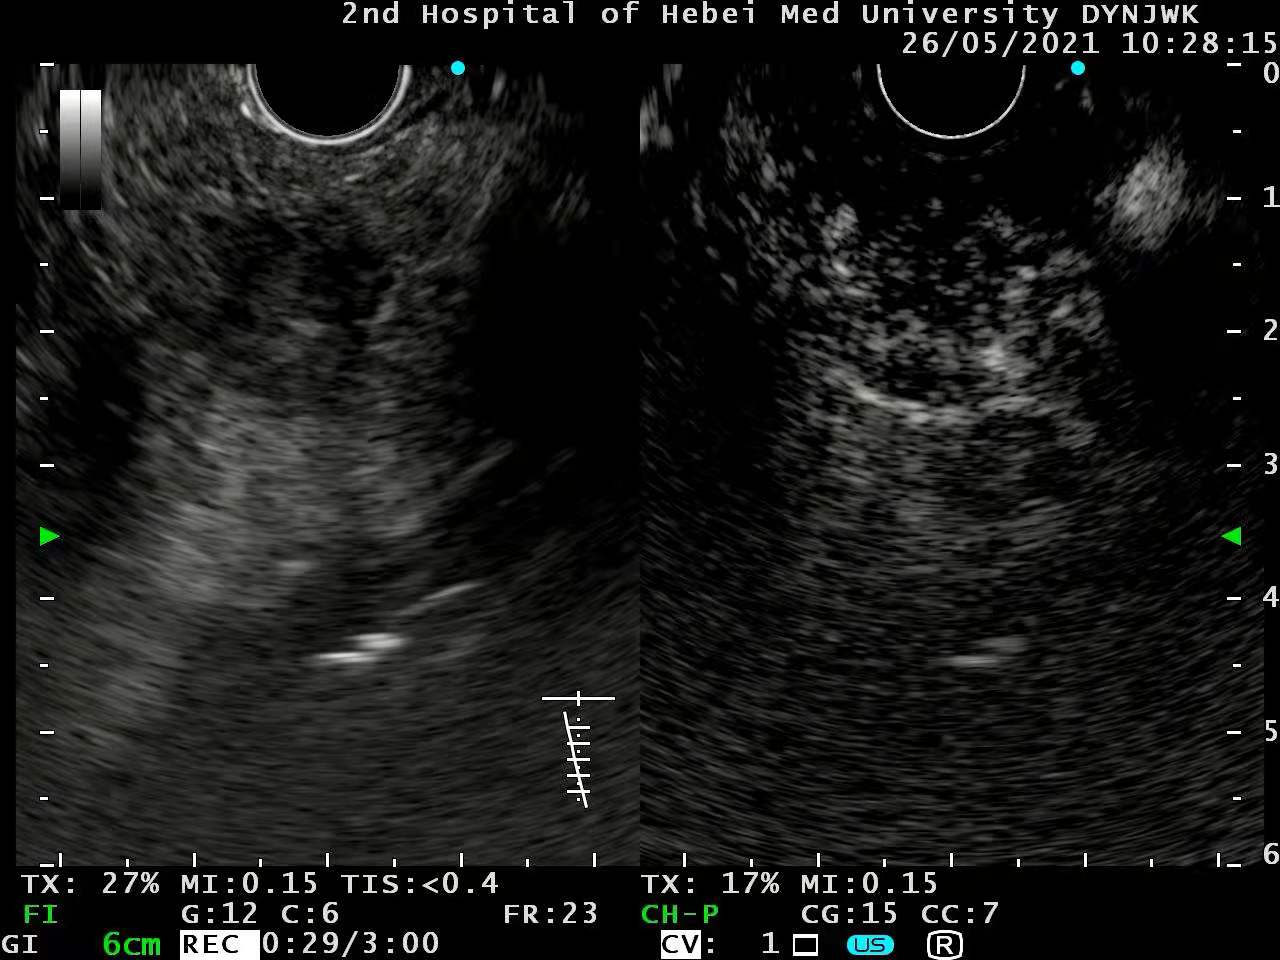

EUS如下:

肿物没有侵犯血管和胰管。

谐波造影提示快速强化。

快速退出。